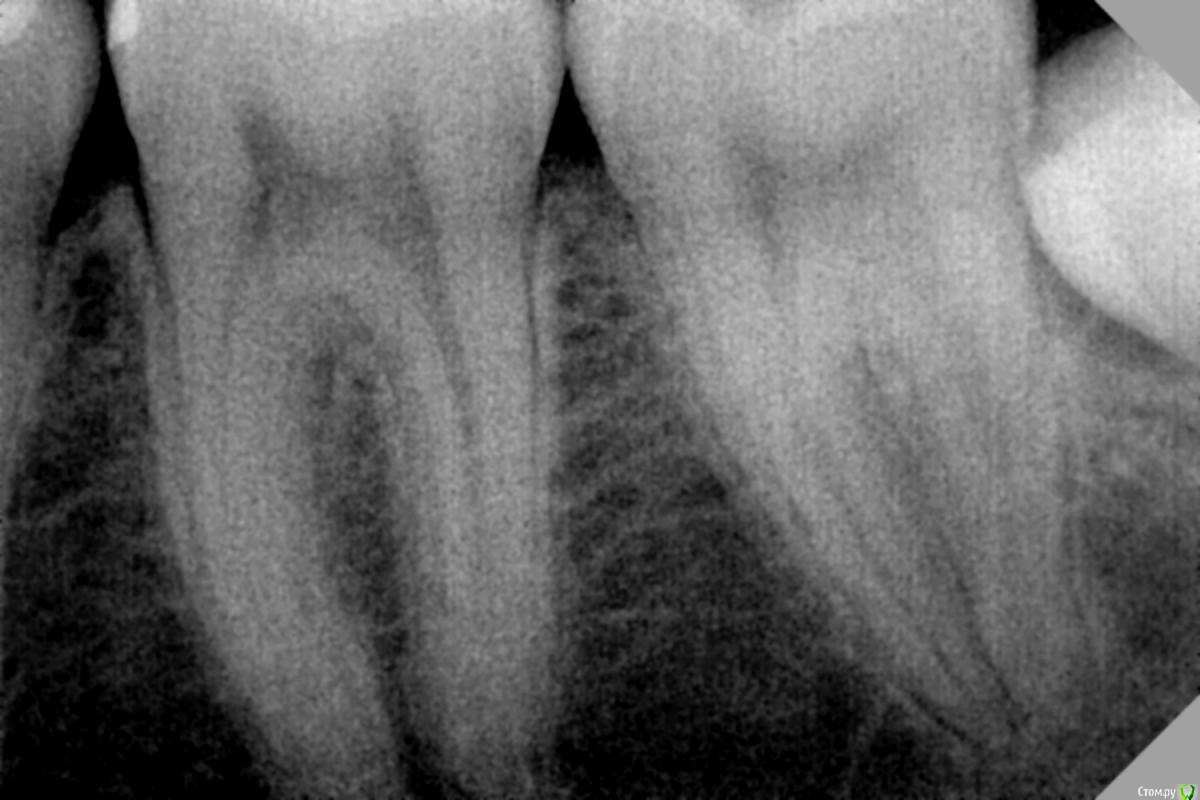

dr.Dre Опубликовано 19 июня, 2017 Поделиться Опубликовано 19 июня, 2017 Добрый день ,пациентка 21 год жалобы на легкую боль на 7 зуб при перкусии на медиальные бугорки может быть причини в 8? Ссылка на комментарий

vse32 Опубликовано 20 июня, 2017 Поделиться Опубликовано 20 июня, 2017 Есть мнение, что лучше все же не удалять при активном течении процесса. Абсолютно согласна, особенно на счет восьмерок. Все до меня проголосовали за удаление восьмерки основываясь на чём? На том, что видать ее уголок? А разве и так не видно, что есть дистопия 38, карман, и риск возникновения резорбции давления у 37?38 зуб представляет угрозу для 37 и будет постоянно доставлять дискомфорт или боли хозяину. Ссылка на комментарий

Saechka09 Опубликовано 21 июня, 2017 Поделиться Опубликовано 21 июня, 2017 Согласна. А еще прибавить карман у коронки 38, да нечто, напоминающее поражение твердых тканей на 37 в месте, где его восьмой ковыряет.... я бы удаляла Ссылка на комментарий